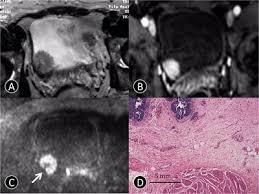

Imaging Diagnosis And Follow Up Of Advanced Prostate Cancer Clinical Perspectives And State Of The Art Radiology

Imaging Diagnosis And Follow Up Of Advanced Prostate Cancer Clinical Perspectives And State Of The Art Radiology from pubs.rsna.org